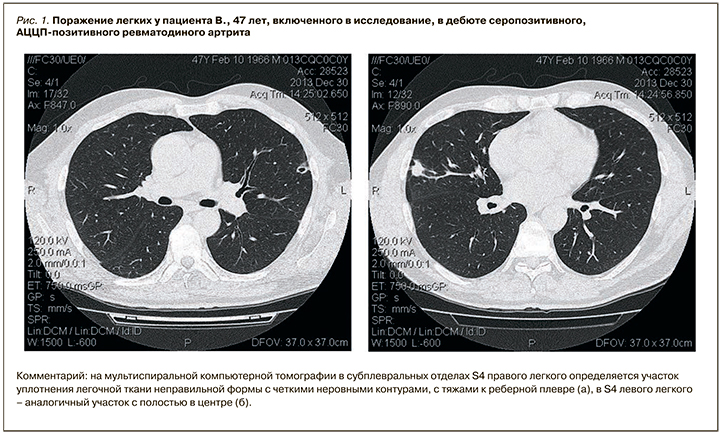

По данным нашего исследования, у АЦЦП-позитивных пациентов достоверно чаще встречались ревматоидные узелки, а в отношении других МСКТ-признаков интерстициального поражения различия оказались статистически незначимыми. Факт того, что большинство различий оказалось недостоверным, также можно объяснить величиной выборки. Однако, на наш взгляд, полученные результаты в большей степени связаны с особенностью дизайна исследования и статистического анализа данных. Это обусловлено тем, что в цитируемых работах [6, 10, 12] осуществлялось сравнение титров АЦЦП у пациентов с клинически манифестированным интерстициальным поражением легких без учета субклинических вариантов, в то время как последние наблюдаются гораздо чаще – у 70–80% больных [11]. Судя по всему, именно это обстоятельство вызывает искажение данных статистического анализа. Не вызывает сомнений, что высокий титр АЦЦП ассоциирован с более тяжелым течением поражения легких [6, 12], но в то же время низкие цифры АЦЦП не исключают развитие субклинического интерстициального поражения легких (рис. 1 и 2).

По данным нашего исследования, у АЦЦП-позитивных пациентов достоверно чаще встречались ревматоидные узелки, а в отношении других МСКТ-признаков интерстициального поражения различия оказались статистически незначимыми. Факт того, что большинство различий оказалось недостоверным, также можно объяснить величиной выборки. Однако, на наш взгляд, полученные результаты в большей степени связаны с особенностью дизайна исследования и статистического анализа данных. Это обусловлено тем, что в цитируемых работах [6, 10, 12] осуществлялось сравнение титров АЦЦП у пациентов с клинически манифестированным интерстициальным поражением легких без учета субклинических вариантов, в то время как последние наблюдаются гораздо чаще – у 70–80% больных [11]. Судя по всему, именно это обстоятельство вызывает искажение данных статистического анализа. Не вызывает сомнений, что высокий титр АЦЦП ассоциирован с более тяжелым течением поражения легких [6, 12], но в то же время низкие цифры АЦЦП не исключают развитие субклинического интерстициального поражения легких (рис. 1 и 2).